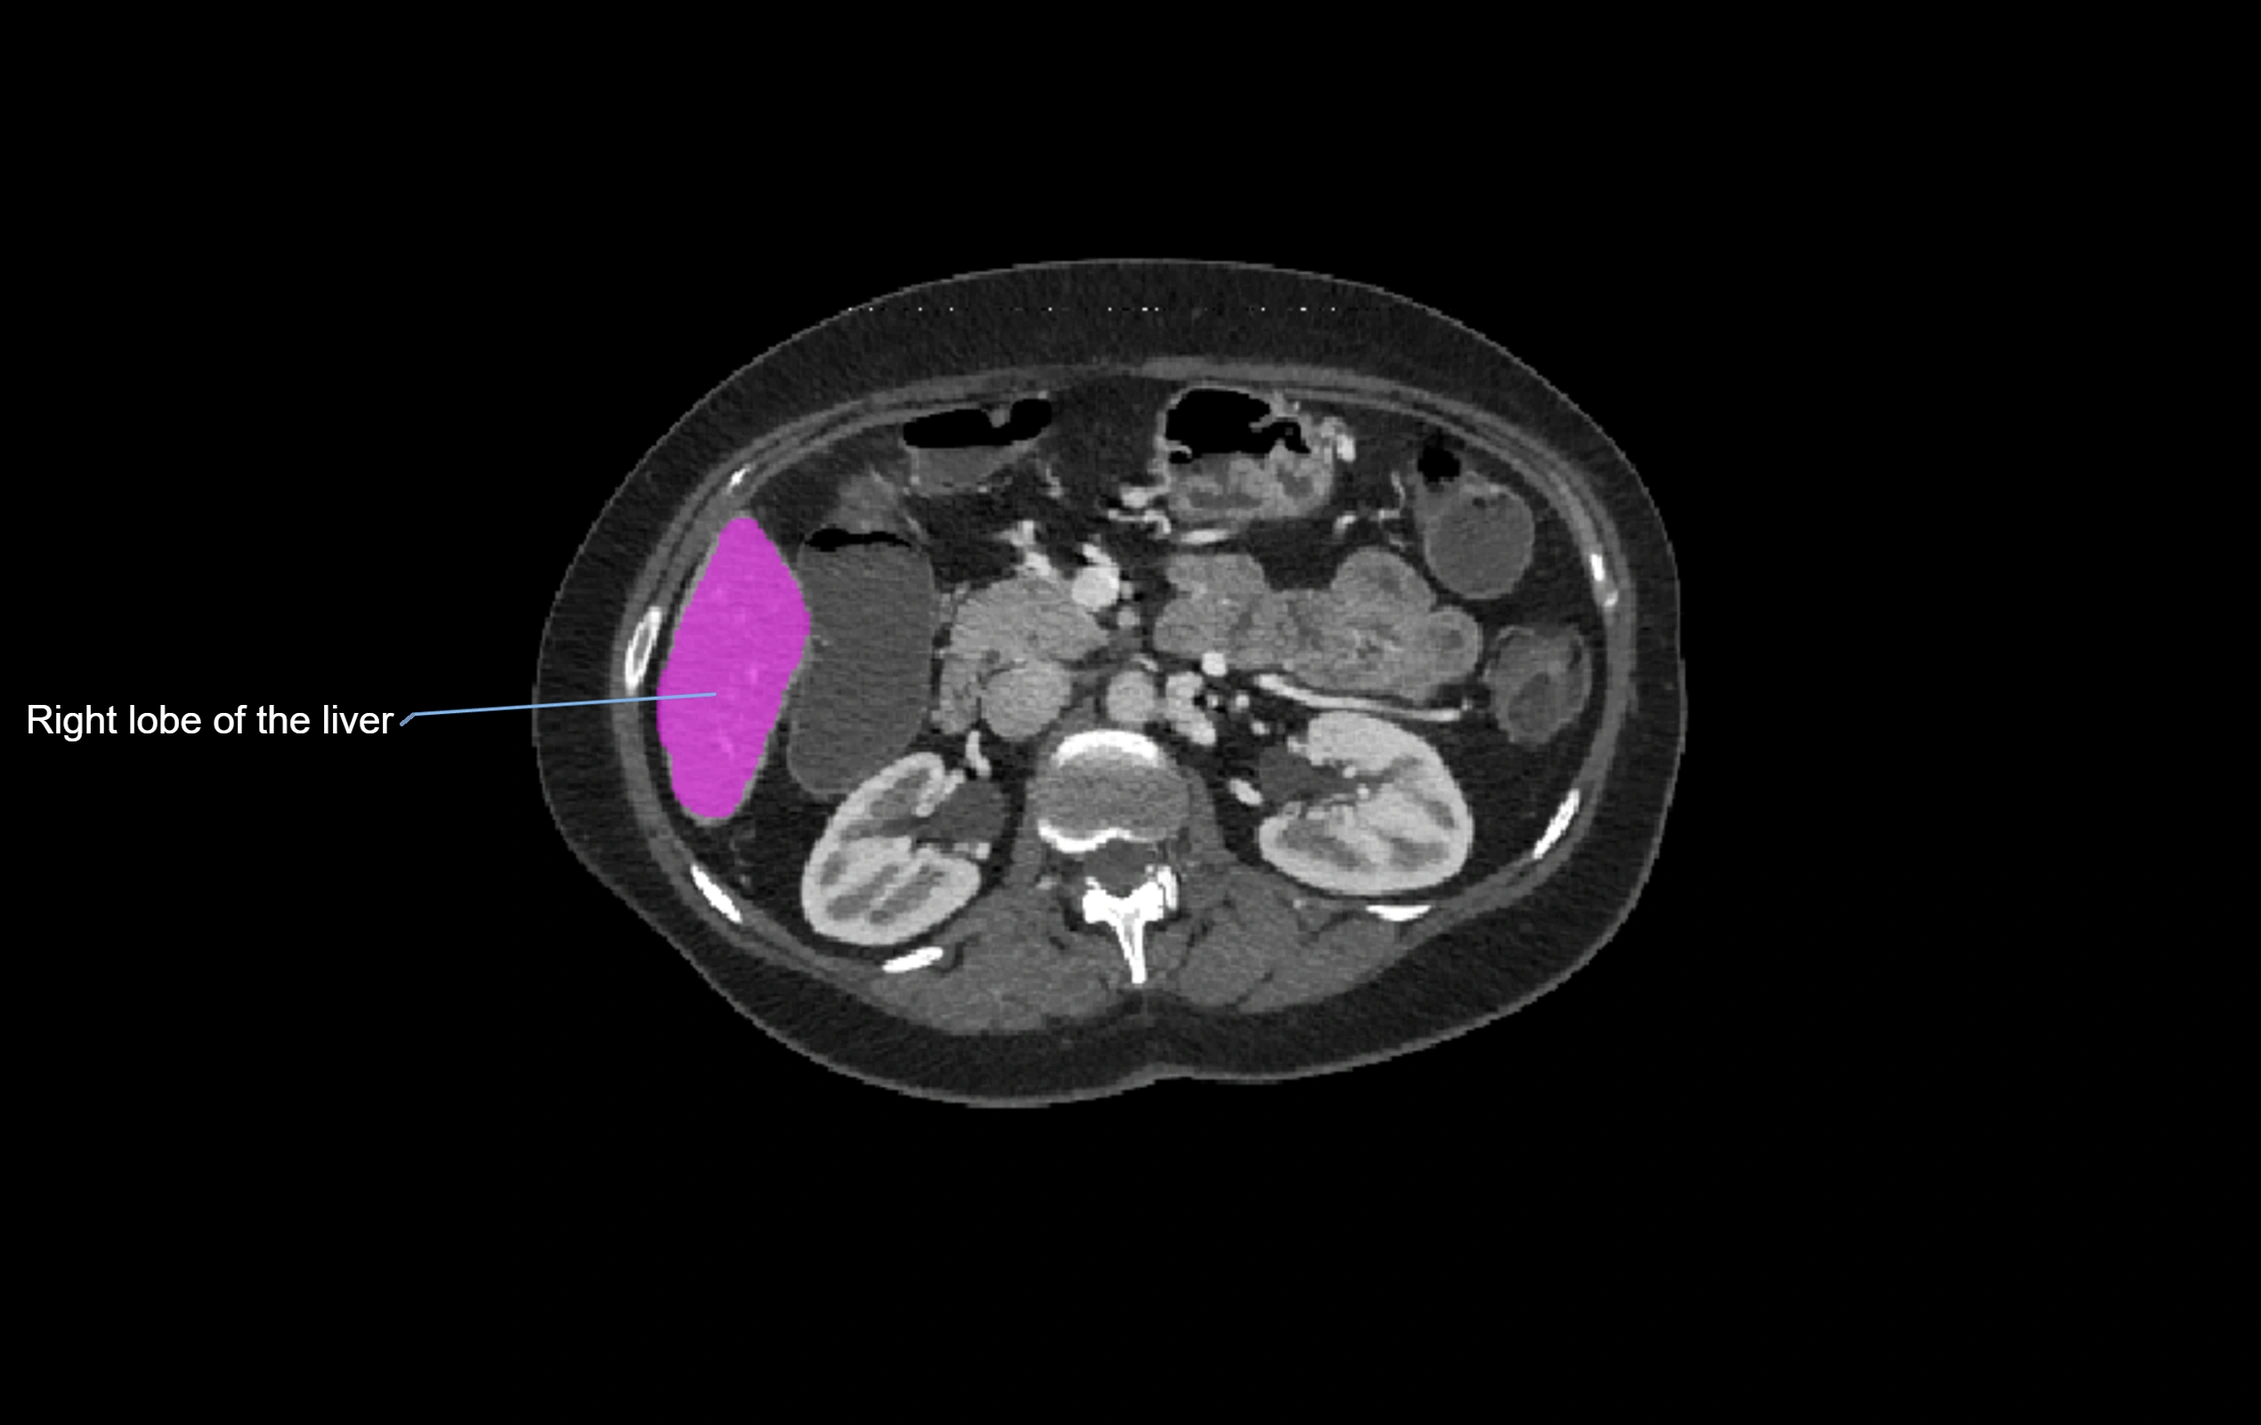

CT Image

image